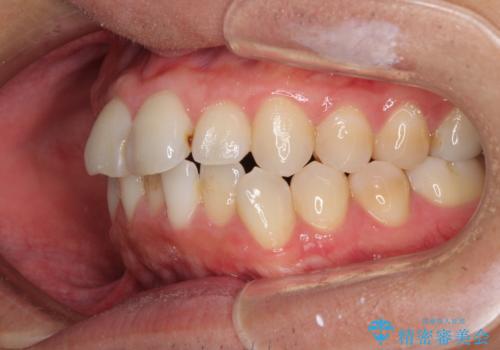

顎が左右にずれた咬み合わせ ハーフリンガルの抜歯矯正

- 口元の突出感を気にして来院された患者様です。

目立たない装置を希望され、上顎が裏側装置で下顎が表側装置のハーフリンガルを希望されました。

上下の顎骨が左右に大きくずれており、奥歯が交叉咬合となっていたため、ハーフリンガルよりも表側装置をおすすめしましたが、目立たない装置を強く希望されたため、治療期間が長期化することを前提に、ハーフリンガルにて抜歯矯正を行うこととしました。